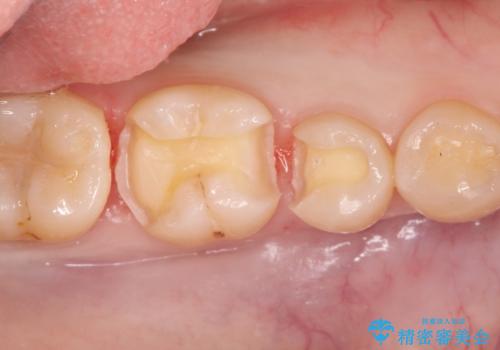

自然な見た目のセラミックインレー

- むし歯の治療を希望されて来院された患者様です。

セラミックインレーによる修復を行っております。

自然な見た目に満足して頂きました。

保険治療で使える材料には制限があり、見た目だけでなく精度でも劣ります。当院でのセラミックインレーは歯とのつなぎ目を拡大鏡で確認して精度高く仕上げるため、むし歯のリスクを限りなく少なくできるよう治療します。